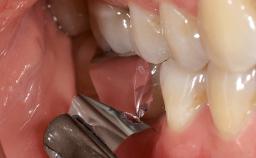

Despite anti-infective surgical treatment, some patients may experience recurrent infection and progressive bone loss requiring additional treatment. Removal of Implant Due to Recurrent Infection describes a conservative approach using an implant retrieval tool without the need for excessive bone removal or use of a trephine.